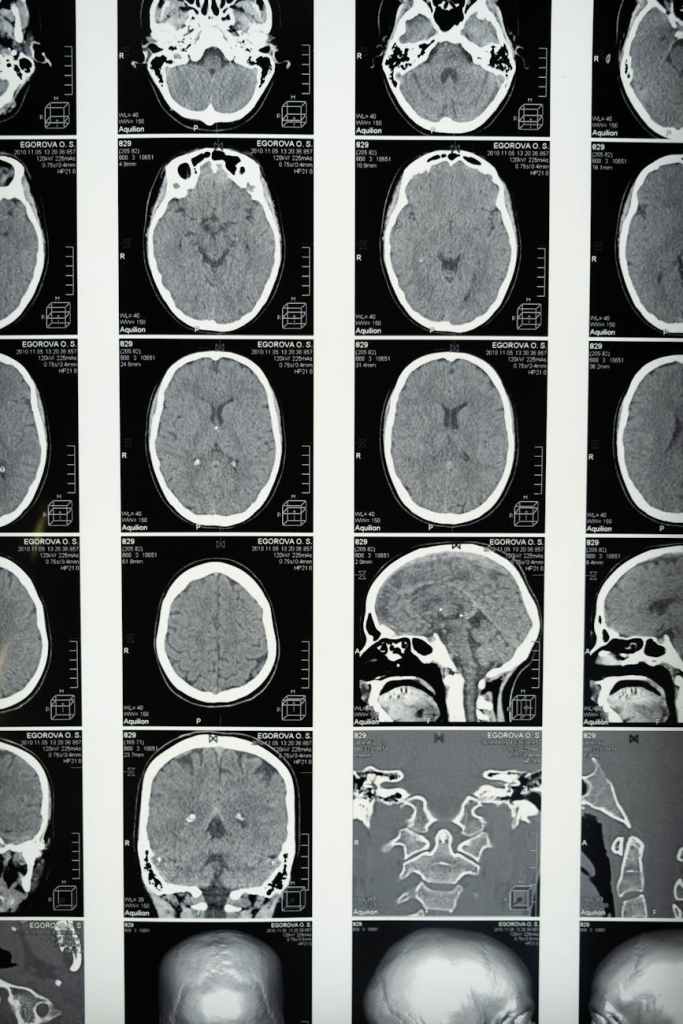

After trauma, your brain’s amygdala, the part responsible for detecting threats goes into overdrive. It starts treating everything as a potential danger, even things that used to feel safe.

Trauma can interfere with the hippocampus, the part of your brain that organizes and stores memories. This is why you might have trouble recalling what happened during the traumatic event, or why certain memories seem to come out of nowhere, as vivid as the day they occurred.